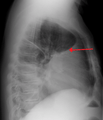

A pleural effusion appears as an area of whiteness on a standard posteroanterior chest X-ray.[5] Normally, the space between the visceral pleura and the parietal pleura cannot be seen. A pleural effusion infiltrates the space between these layers. Because the pleural effusion has a density similar to water, it can be seen on radiographs. Since the effusion has greater density than the rest of the lung, it gravitates towards the lower portions of the pleural cavity. The pleural effusion behaves according to basic fluid dynamics, conforming to the shape of pleural space, which is determined by the lung and chest wall. If the pleural space contains both air and fluid, then an air-fluid level that is horizontal will be present, instead of conforming to the lung space.[6] Chest radiographs in the lateral decubitus position (with the patient lying on the side of the pleural effusion) are more sensitive and can detect as little as 50 mL of fluid. At least 300 mL of fluid must be present before upright chest X-rays can detect a pleural effusion (e.g., blunted costophrenic angles).

A pleural effusion as seen on lateral upright chest x ray